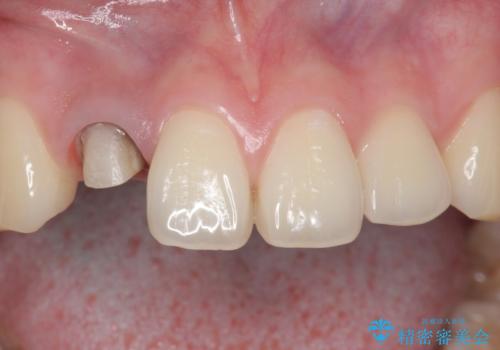

精査したところ、透過性のあるセラミッククラウンで治療されており、内側の黒い土台が透けてクラウンが黒ずんで見えていました。

土台を白いファイバーコアにやりかえたのち、土台の色を透過させないジルコニアフレームを用いたセラミッククラウンによる治療を行いました。